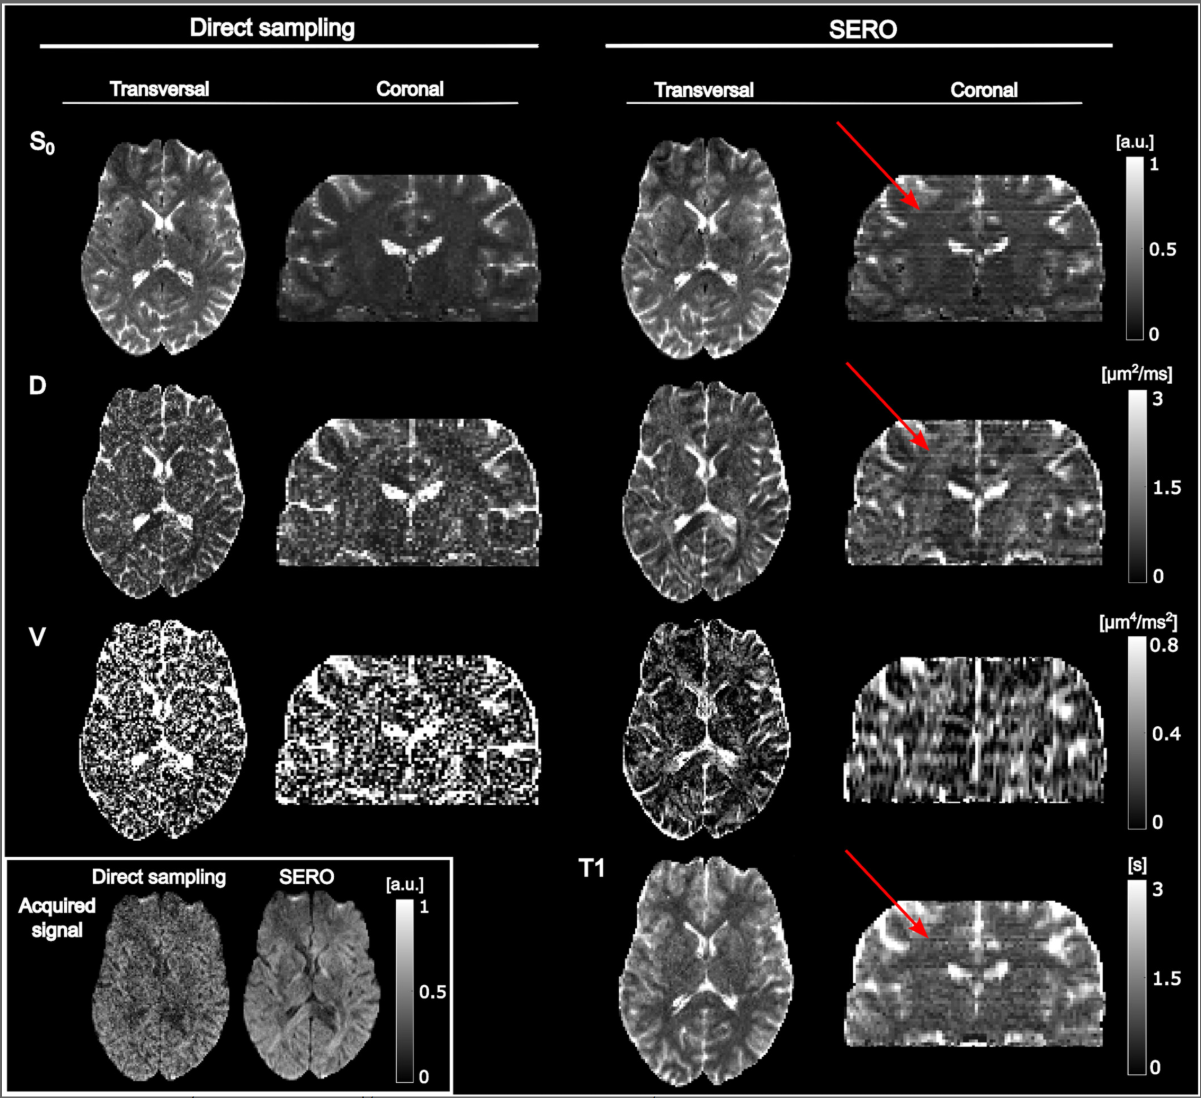

Na to pytanie odpowiada artykuł "Toward Super Resolution Reconstruction of Diffusion-Relaxation MRI Using Slice Excitation With Random Overlap (SERO)", autorstwa Felixa Mortensena, Jakuba Jurka, Jensa Sjölunda, Geraline Vis, Ronniego Wirestama, Malwiny Molendowskiej, Andrzeja Materki i Filipa Szczepankiewicza.

🔬 W publikacji poruszono zagadnienie uzyskiwania obrazu o wysokiej rozdzielczości na podstawie wielu obrazów o niskiej rozdzielczości - czyli tzw. rekonstrukcji nadrozdzielczej.

📌 Proponowana metoda zakłada szybkie skanowanie mózgu i uzyskanie aż 1000 przekrojów o losowym położeniu i grubości 6 mm. Dane te są następnie łączone za pomocą modelu matematycznego, który przetwarza je na 40 przekrojów o grubości 1,5 mm.

Co więcej, każdy przekrój rekonstruowany jest w czterech typach kontrastu, zależnych od:

• gęstości protonowej,

• tkankowej stałej czasowej T1,

• dyfuzyjności,

• wariancji dyfuzyjności cząsteczek wody.

🧪 Badania przeprowadzono na obrazach mózgu i stanowią ważny krok w rozwoju nowoczesnych technik MRI.